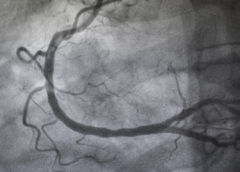

LeggiAngiografia: CO2 come mezzo di contrasto per salvaguardare i reni

Utilizzare come mezzo di contrasto in una angiografia l’anidride carbonica al posto di un liquido contenente iodio. Ad utilizzare l’innovativa tecnica in grado di abbattere il rischio di danno renale correlato all’esame sono i medici dell’ospedale San Giovanni di Dio di Firenze, unica struttura…